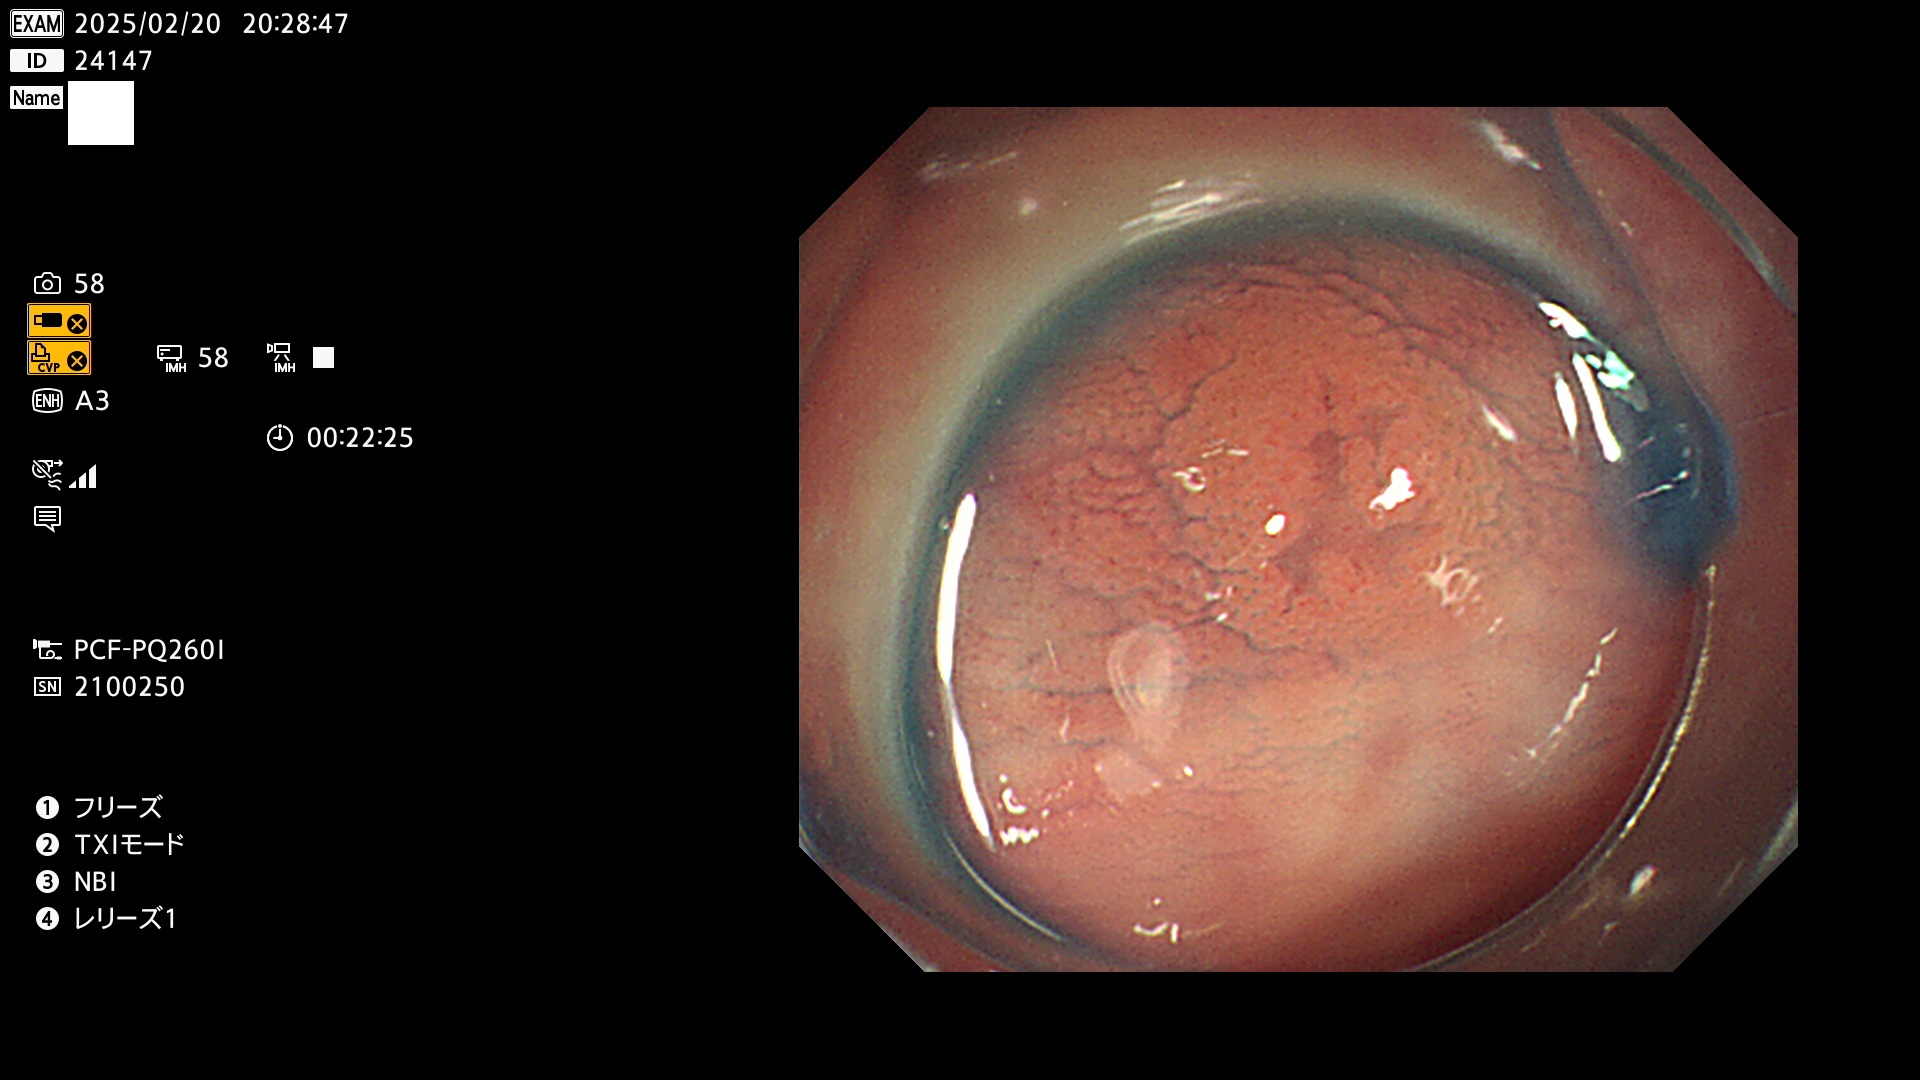

完全に平坦な物をUb、陥凹している物をUcと呼びます。最も発見が難しく危険な病変です。

毎週の検査(木・金・土・日)に発見されたUb、Uc型・腺腫を、その週の日曜の夜にUPし1週間、提示します。

抽出の対象期間 2025年2月20日〜2月23日の4日間(48件の検査)8個 (8/48=16%)